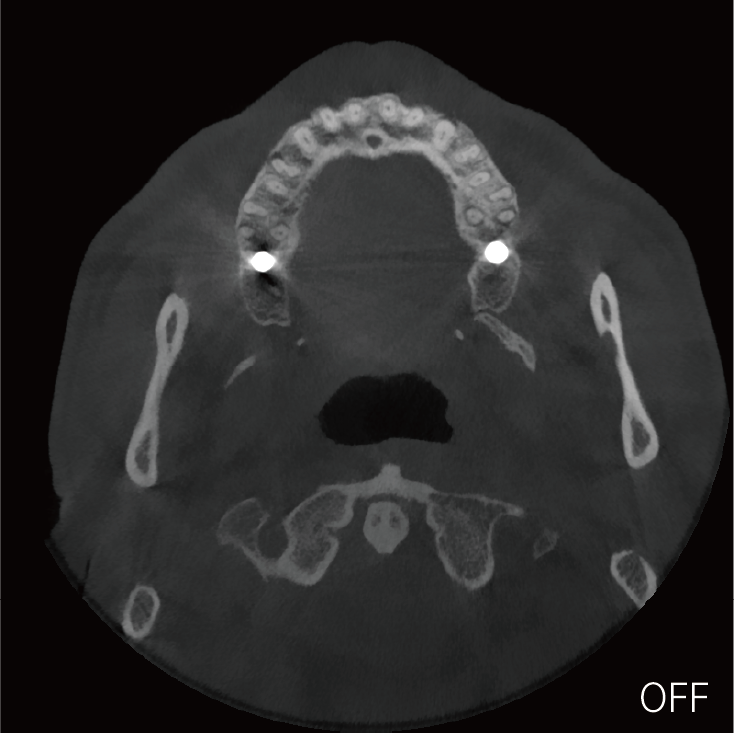

超能去伪 至臻影像

局部超清显示、 移动视野摄片

可根据临床需求任意调整成像区域大小实现局部超清三维显示

临床样片